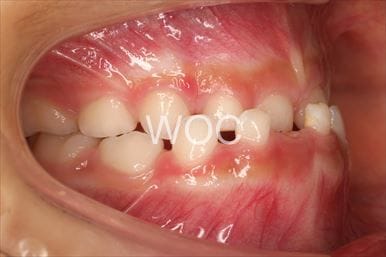

治療前1

治療前2

治療前3

治療前4

治療前5

- 年齢:8歳2ヶ月

- 主訴:ガタガタ

- 診断名:叢生、上顎前突、過蓋咬合

- 装置:機能的矯正装置

- 期間:6年5ヶ月 ※

- 費用:基本矯正料金:350,000円